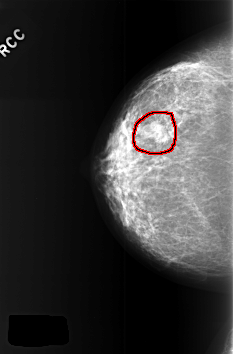

C_0377_1.RIGHT_CC

RIGHT_CC LINES 5664 PIXELS_PER_LINE 3728 BITS_PER_PIXEL 12 RESOLUTION 50 OVERLAY

FILE: C_0377_1.RIGHT_CC.OVERLAY

TOTAL_ABNORMALITIES 1

ABNORMALITY 1

LESION_TYPE MASS SHAPE LOBULATED MARGINS OBSCURED

ASSESSMENT 4

SUBTLETY 4

PATHOLOGY BENIGN

TOTAL_OUTLINES 1

BOUNDARY